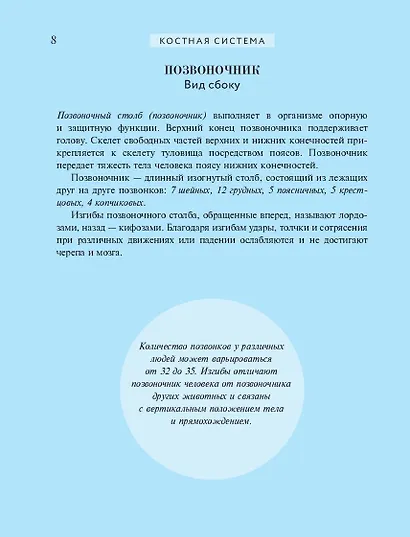

«Популярный атлас анатомии человека» — это оптимальный объем базовых знаний о строении человеческого тела. Созданная современными учеными-анатомами с использованием новейших данных, книга предлагает четко структурированную информацию, изложенную в 10 тематических главах по основным анатомическим системам.

Особую ценность изданию придают высококачественные репродукции классических гравюр из знаменитой «Gray's Anatomy» — самого известного англоязычного учебника по анатомии человека. Более 200 классических иллюстраций выполнены с безупречной детализацией благодаря современным полиграфическим технологиям. Винтажные гравюры XIX века сочетаются с удобным компактным форматом и ярким дизайном, что делает книгу одновременно эстетически привлекательной и практичной в использовании.

"Популярный атлас анатомии человека" — это доступное, красочное и информативное издание, содержащее основные сведения о строении человеческого тела. Написанный ведущими учёными-анатомами с учётом последних научных данных, атлас предлагает систематизированную информацию, разделённую на 10 глав по ключевым анатомическим системам. Книга сочетает в себе ясность изложения и высокое качество визуального материала: она проиллюстрирована классическими гравюрами из знаменитой "Анатомии Грея", что делает изучение анатомии наглядным и увлекательным. Удобный компактный формат практичен в использовании,а цветная печать изображений обеспечивает комфортное чтение и детальное рассмотрение иллюстраций из всемирно известного медицинского учебника.